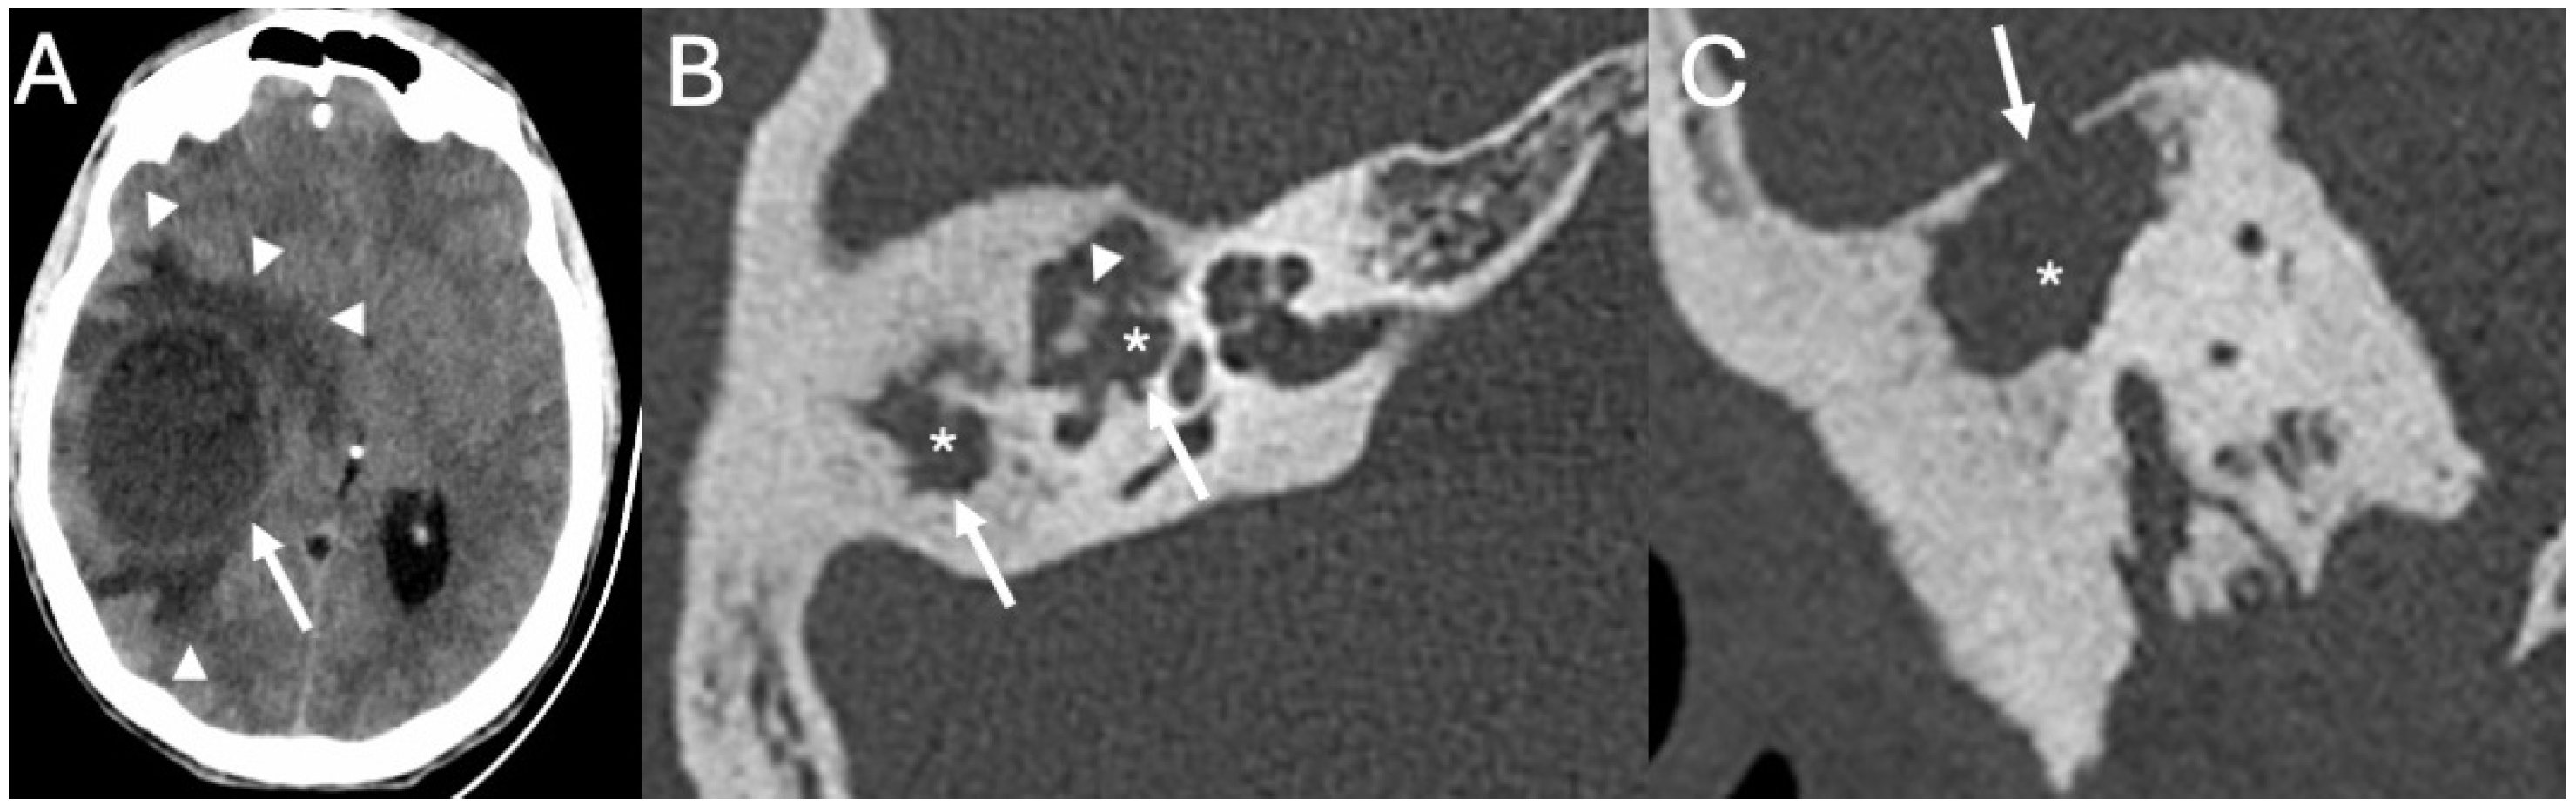

3.1. Otomastoiditis

3.1.1. Imaging

3.1.2. Managment